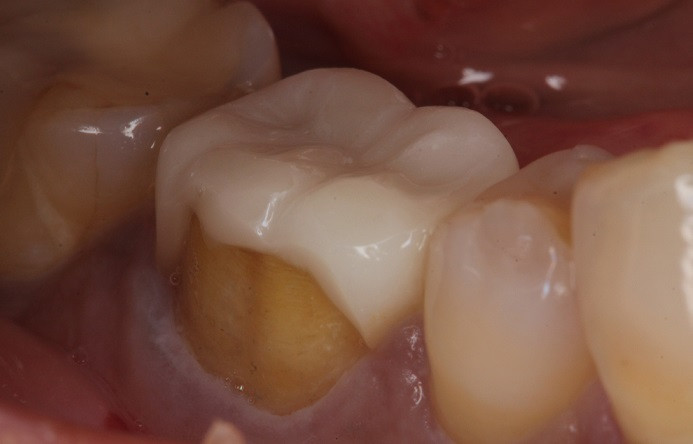

歯の被せ物に関するトラブルでの受診が増えてきています。画像は「1年程前に装着したばかりのセラミックスの被せ物が割れた」という相談で来院された患者様です。

画像のように、材料として適切な厚みを確保できていなければ、欠けてしまうことがあります。また、欠けた欠片や歯の面を見てみると、接着剤が残っていないことが確認されました。本症例では、適切な厚みが確保されていないままに被せ物が製作され、かつ接着剤が早期に脱落してしまったために破損してしまった、と考えられます。